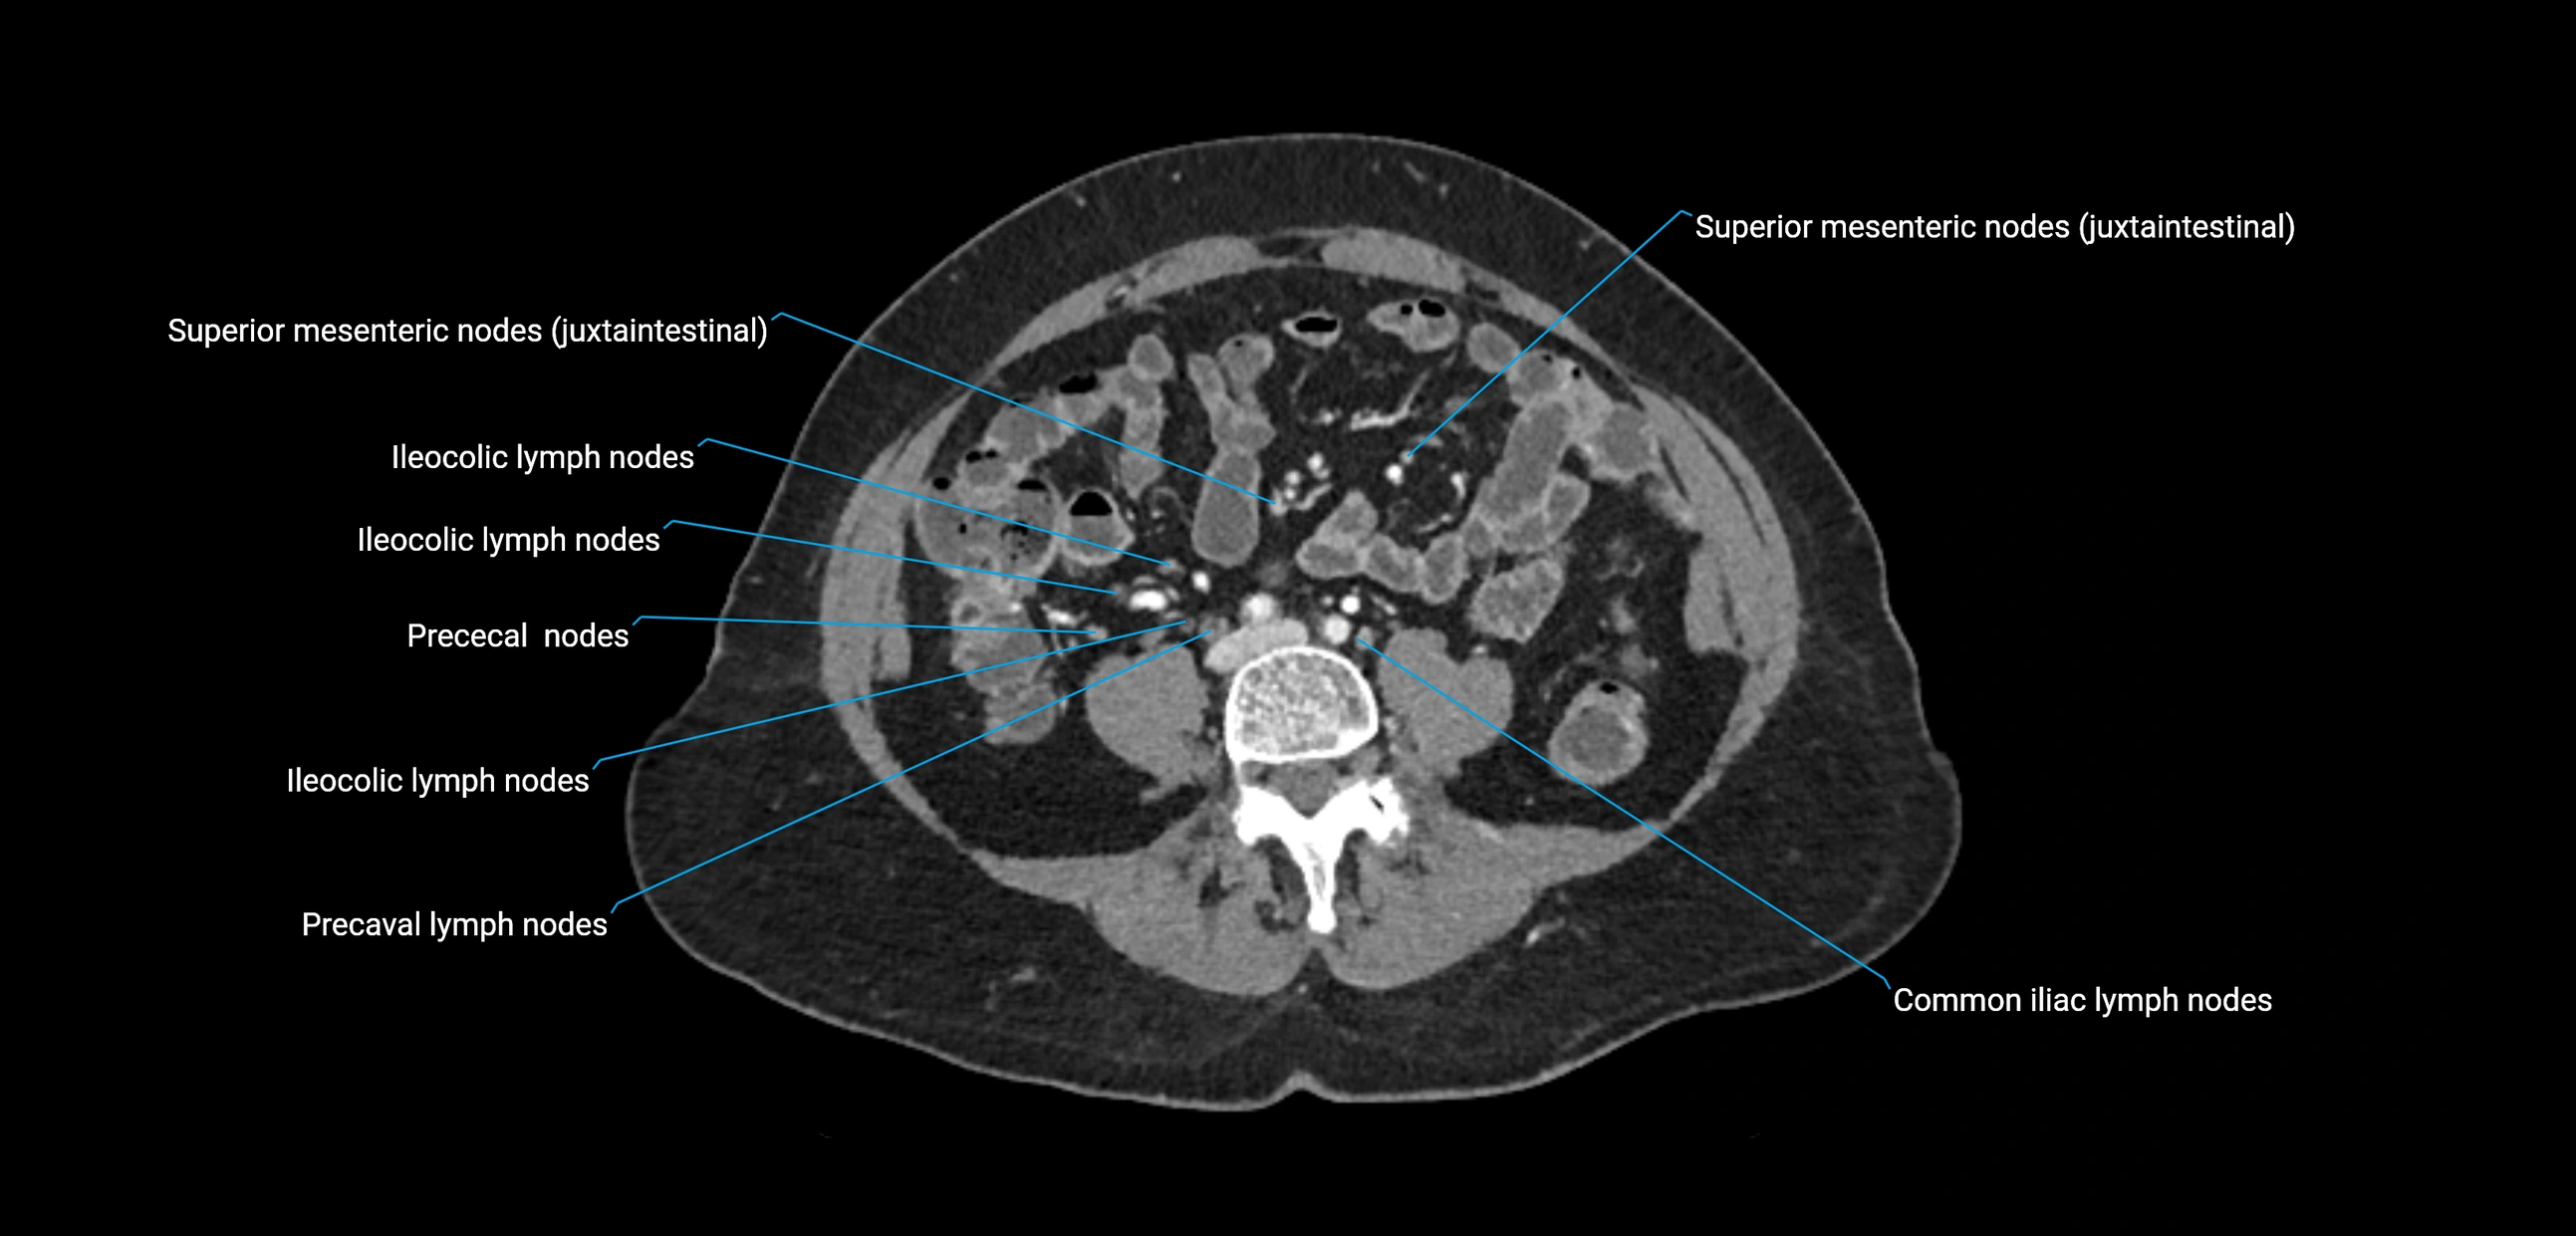

CT Appearance

CT Pre-Contrast:

• Nodes appear as soft-tissue density nodules adjacent to the aorta and IVC

• Calcification may be seen in chronic infections (e.g., tuberculosis)

CT Post-Contrast:

• Normal nodes enhance homogeneously

• Malignant nodes may show heterogeneous enhancement, central necrosis, or conglomerate formation

• Size >1 cm short axis is suspicious, though morphology and distribution are equally important

CT Venography (CTV):

• Demonstrates nodal encasement or compression of adjacent vessels (aorta, IVC, renal veins)

• Useful in staging testicular and ovarian malignancies

• Provides 3D reconstructions for retroperitoneal lymph node dissection planning

CT image

image